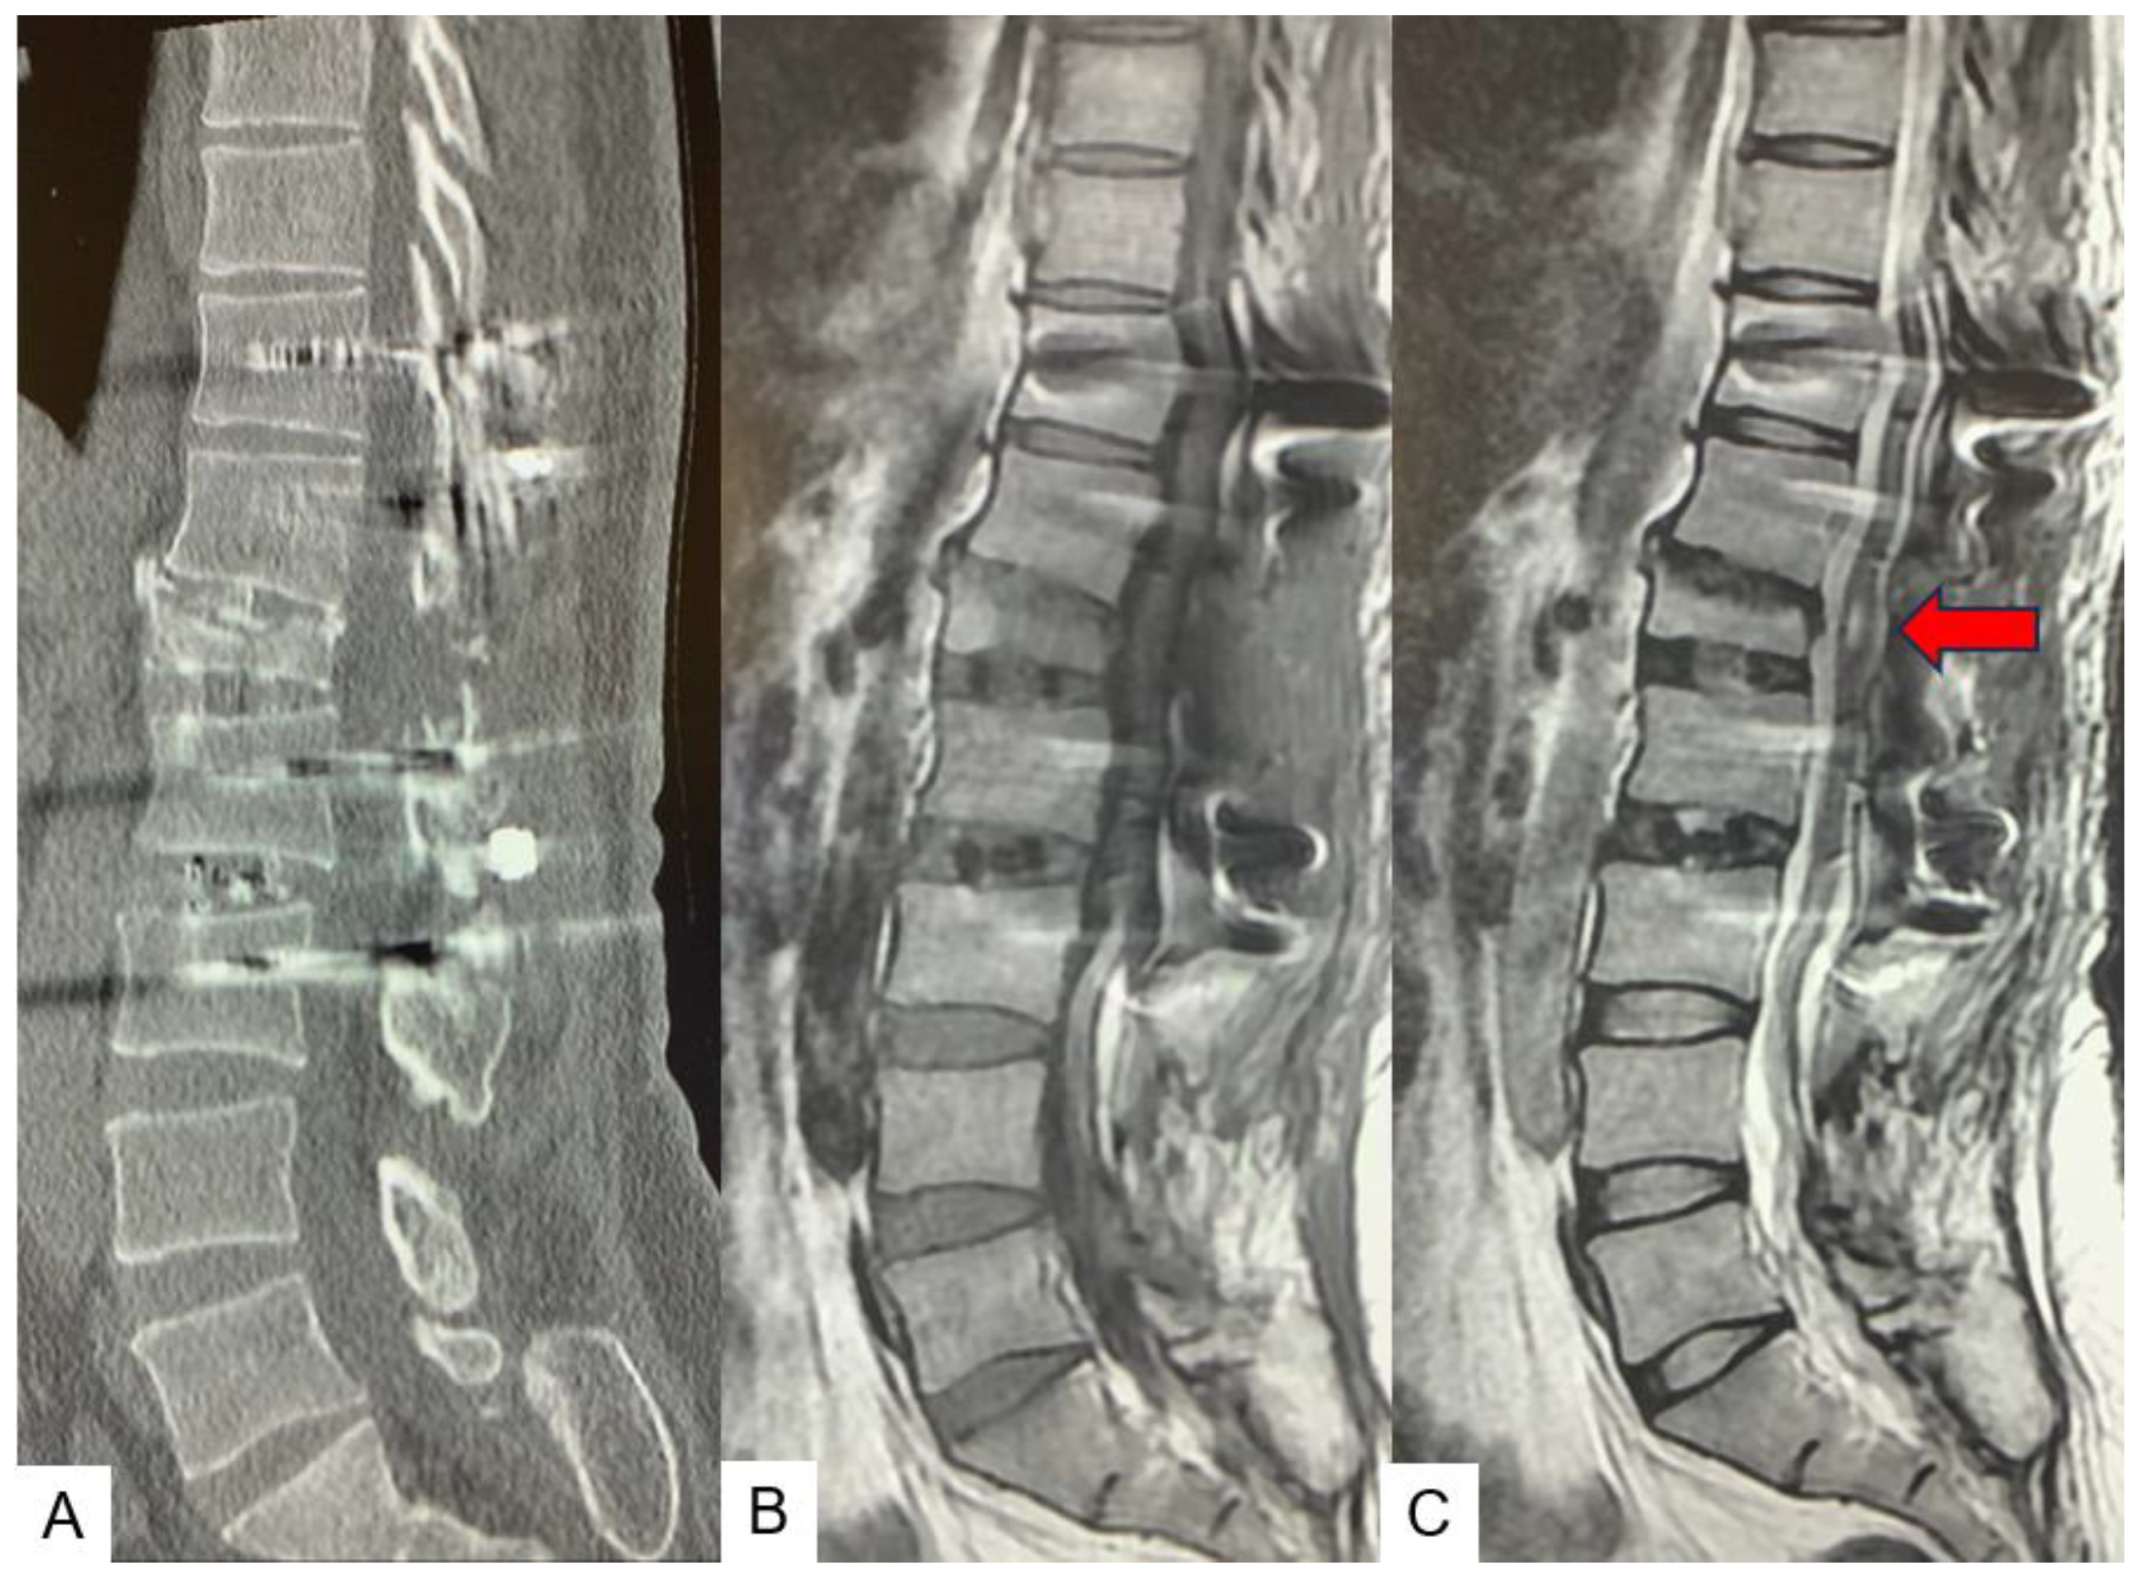

3. Case 2 33 years old male, tethered cord syndrome, conventional technique